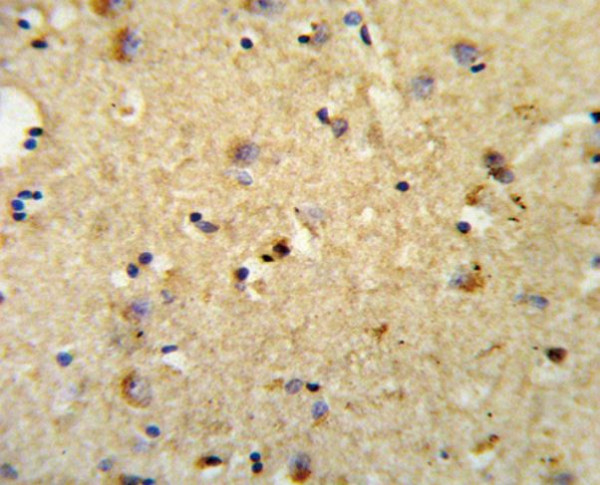

Product information "Anti-OLR1 / LOX-1"

Protein function: Receptor that mediates the recognition, internalization and degradation of oxidatively modified low density lipoprotein (oxLDL) by vascular endothelial cells. OxLDL is a marker of atherosclerosis that induces vascular endothelial cell activation and dysfunction, resulting in pro-inflammatory responses, pro- oxidative conditions and apoptosis. Its association with oxLDL induces the activation of NF-kappa-B through an increased production of intracellular reactive oxygen and a variety of pro- atherogenic cellular responses including a reduction of nitric oxide (NO) release, monocyte adhesion and apoptosis. In addition to binding oxLDL, it acts as a receptor for the HSP70 protein involved in antigen cross-presentation to naive T-cells in dendritic cells, thereby participating in cell-mediated antigen cross-presentation. Also involved in inflammatory process, by acting as a leukocyte-adhesion molecule at the vascular interface in endotoxin-induced inflammation. Also acts as a receptor for advanced glycation end (AGE) products, activated platelets, monocytes, apoptotic cells and both Gram-negative and Gram- positive bacteria. [The UniProt Consortium]

| Application: | WB |